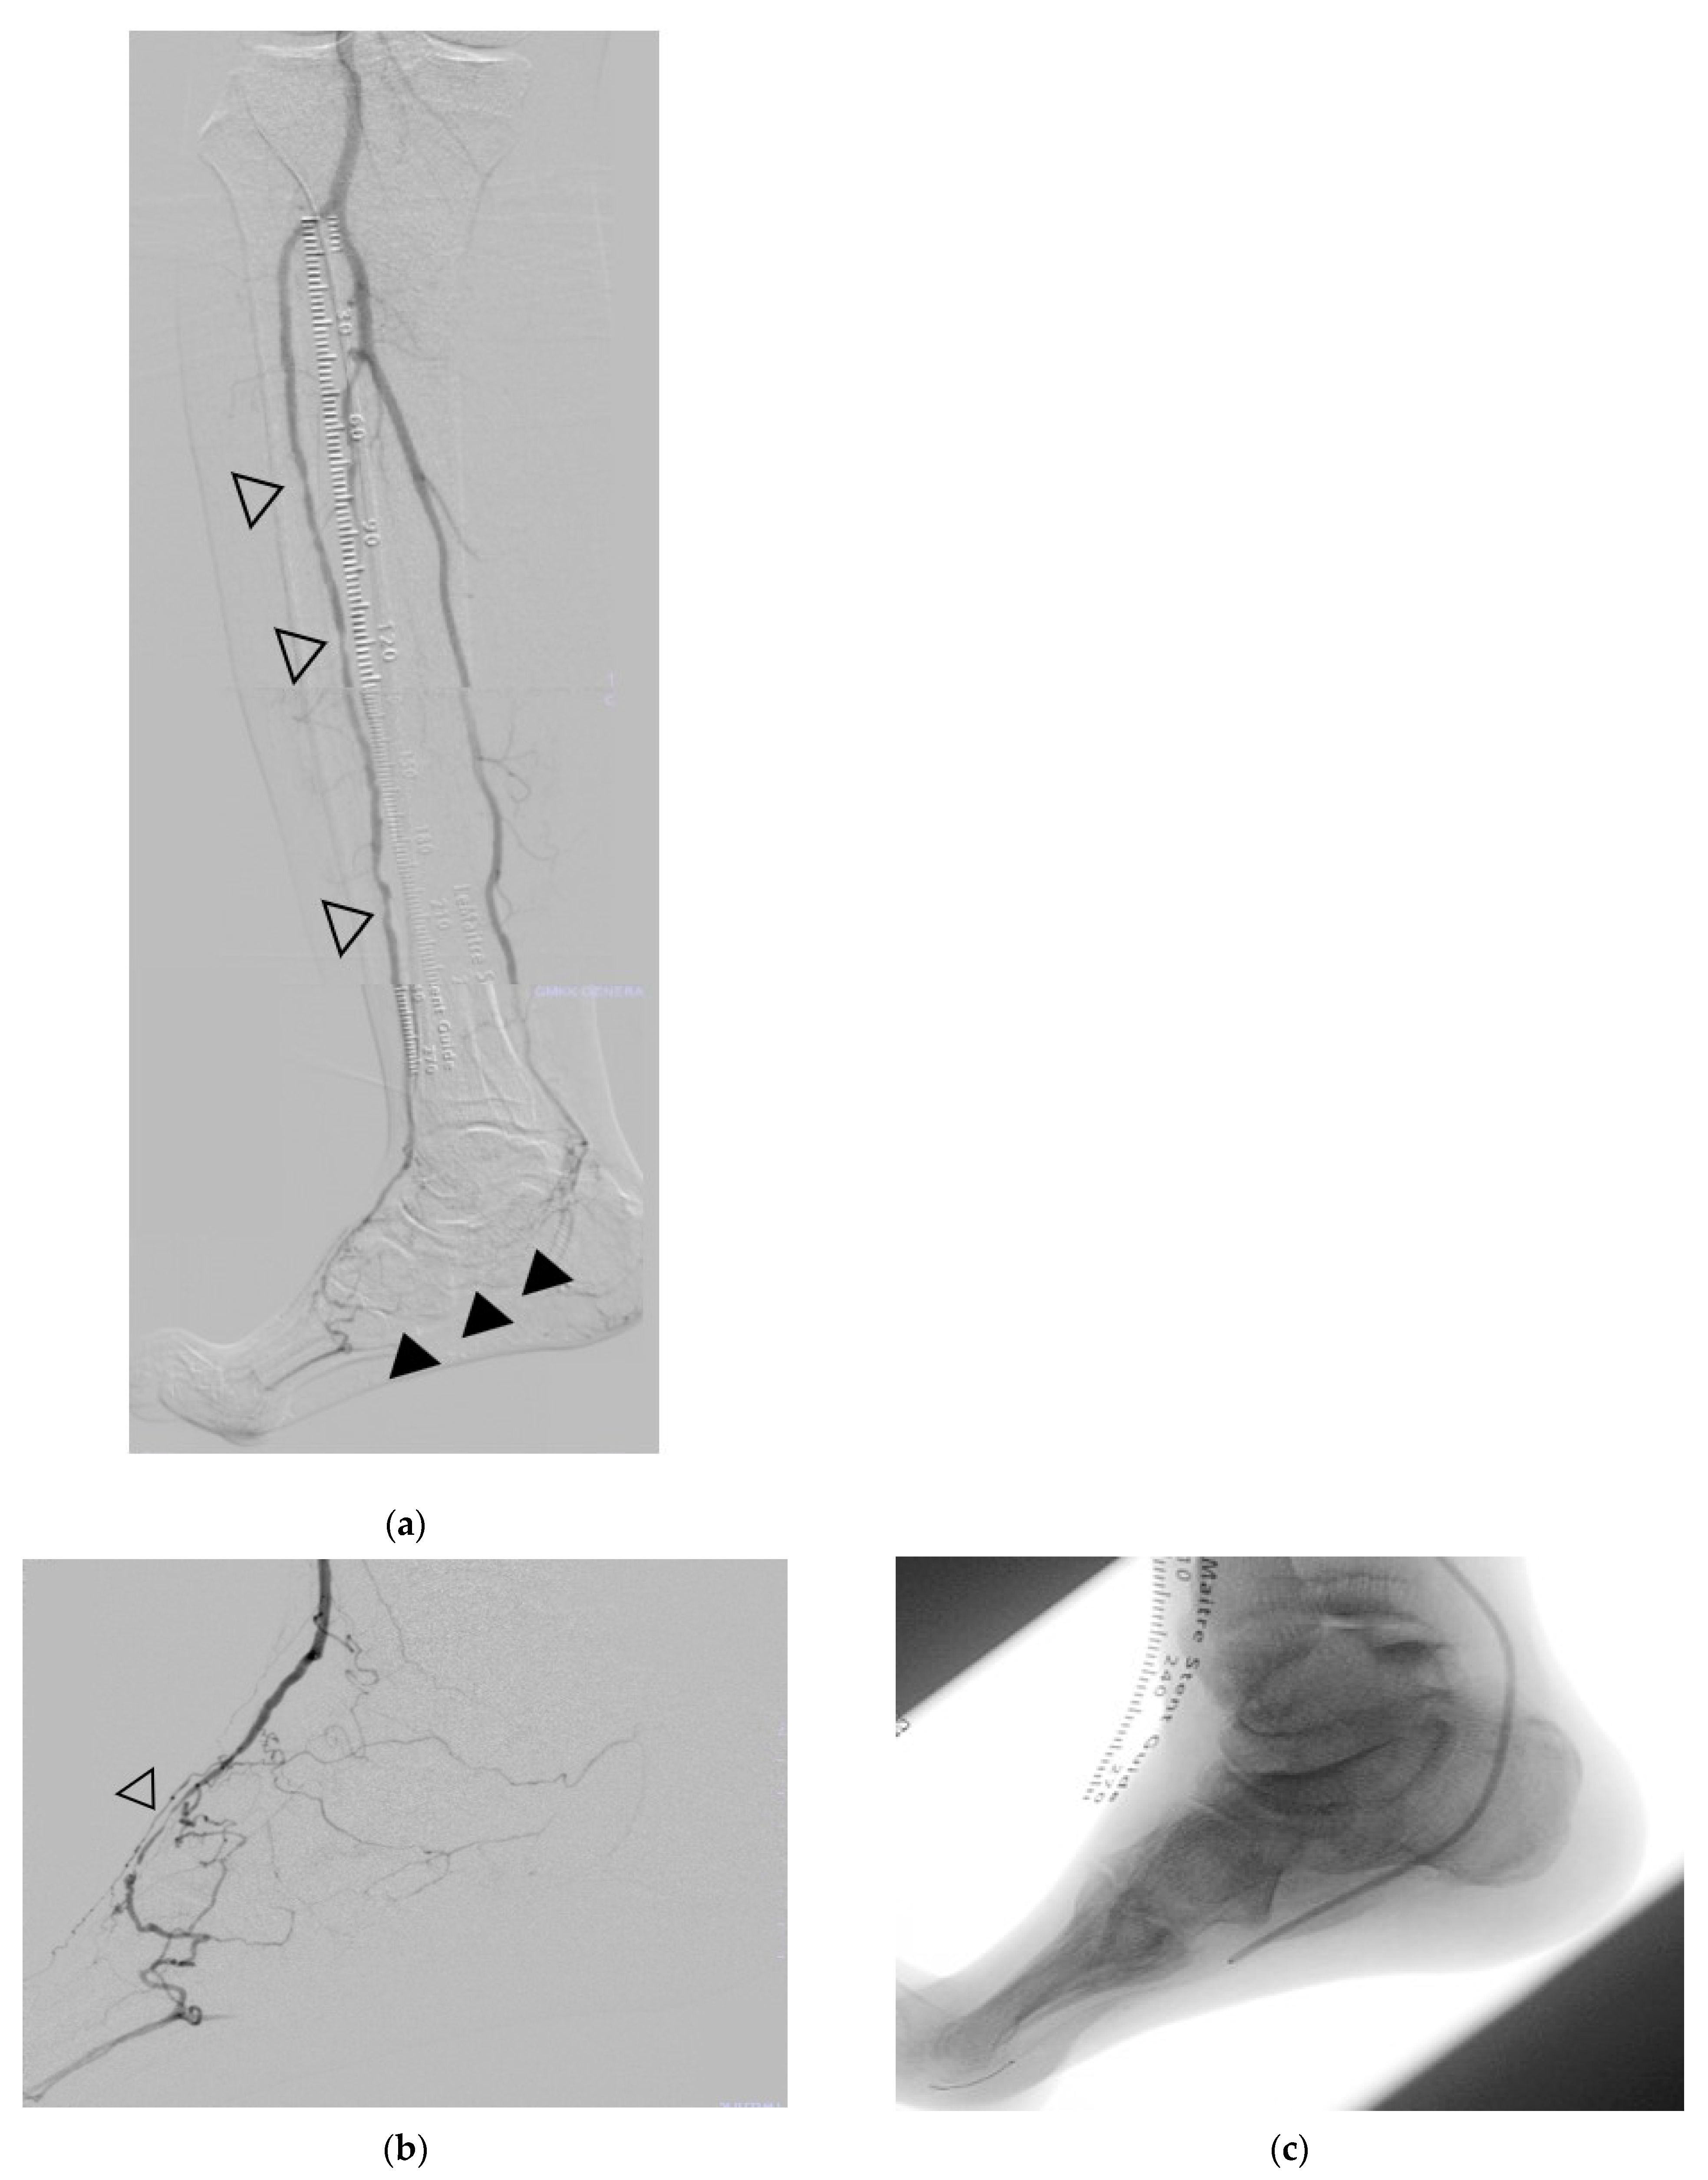

2.3. Revascularization